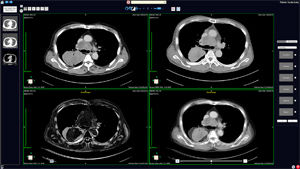

特徴的な機能のひとつに,位置ズレの補正や非剛体の重ね合わせも可能な,独自開発のレジストレーションがある。ボタンひとつで現在の画像と過去画像を重ね合わせて表示することができ,疾患の経時的変化の把握,計測ができる。複数モダリティの画像やスライス厚の異なる画像,また異なる装置メーカーの画像もレジストレーションが可能である。さらに,患者主体のレポート作成機能により,複数モダリティの画像をボリュームデータとして,自由なレイアウトで一画面に表示することも可能となり,医師の読影や診断業務を支援する。

PHOENIXは,レジストレーションビューアとしての側面が強く,画像処理機能を絞り込んでいるが,ボタンひとつでリンクさせた現行のVirtualPlaceに切り替えることで,より高度な画像処理が可能となる。

![]() AZE VirtualPlace PHOENIXによる過去画像とのレジストレーション |

![]() AZE VirtualPlace PHOENIXの同一患者画像比較画面 |